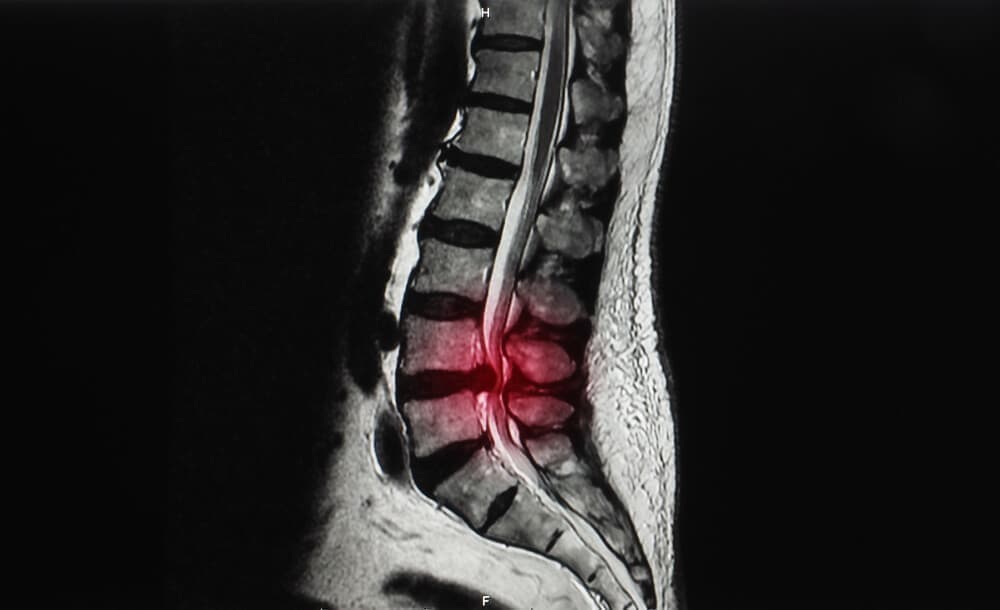

脊柱管狭窄症とは?

体を支える脊柱は、椎骨という骨が連結してできています。

その椎骨には穴が存在し、脊柱として形成されたときには脊柱管という脊髄・血管が走る道が作られます。

その脊柱管が加齢や何かの要因でズレが生じ狭まったときに発症するのが脊柱管狭窄症です。

脊柱管が狭くなると、内部を走っている脊髄や血管が押し付けられます。

それにより

痛みやしびれといった症状が現れます。